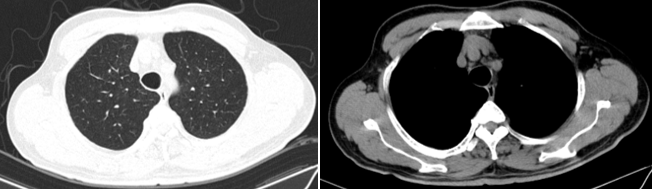

- Chụp cắt lớp vi tính lồng ngực:

Hình 2: Hình ảnh chụp cắt lớp vi tính ngực: chưa phát hiện tổn thương nghi ngờ thứ phát